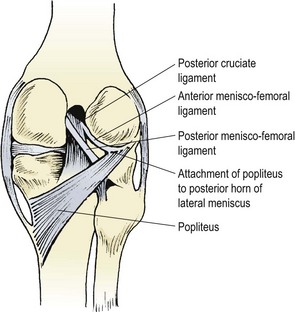

The menisci 189

Injury 191

Management 192

Meniscal cysts and discoid meniscus 194